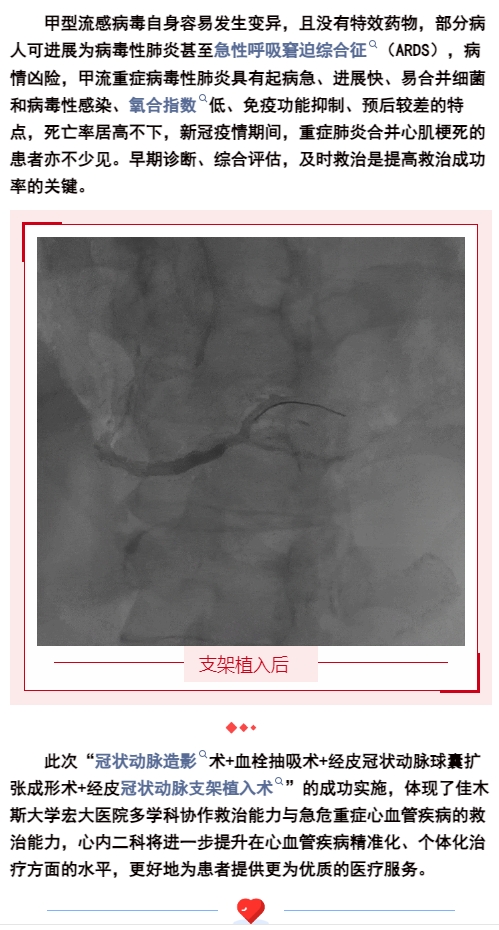

1719194065905972.jpg